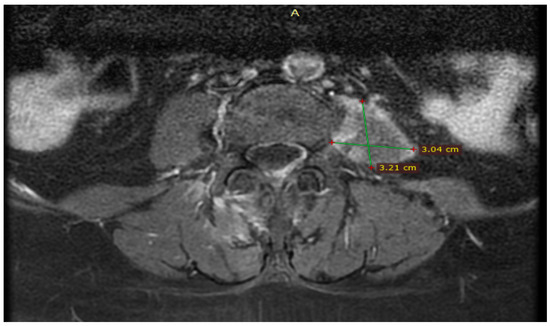

Further, the abdominal and pelvis CT scan with contrast substance showed the cholelithiasis observed on abdominal ultrasound with common bile duct diameter in normal limit values and fused abscess-type collections at the interfibrillar level of the left iliopsoas muscle. The CT also shows hepatomegaly with cranio-caudal dimensions of the right hepatic lobe of 220 mm, a clear, regular outline, a homogeneous structure, and a cholecyst with multiple calculi up to 17 mm (Figure 3).

Figure 3.

Collections of fused abscesses at the interfibrillar level of the left psoas muscle that cause volumetric growth (4.53/4.75 cm) compared to the contralateral side and associate densifications in the adjacent fatty tissue.